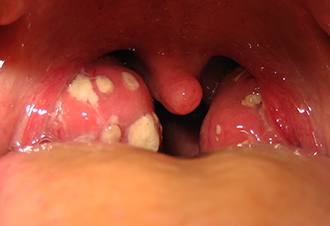

Хронический тонзиллит, хотя и локализован в области миндалин, влияет на весь организм. Люди, страдающие этим заболеванием длительное время, сталкиваются с различными последствиями хронической инфекции: астеническим синдромом, нарушениями работы сердца, сосудов и почек, а также сопутствующими заболеваниями, такими как парафарингит и паратонзиллярный абсцесс. Лечение следует начинать как можно раньше. Как избавиться от гнойных пробок в горле? Тактика терапии зависит от классификации форм хронического тонзиллита:

Если у пациента диагностирована токсико-аллергическая форма второй степени, то тонзиллэктомия становится единственным эффективным методом коррекции состояния. Степень тяжести патологических изменений увеличивается, и возникают новые осложнения. Миндалины теряют свои полезные функции и становятся очагом хронического воспаления и источником бактериальных токсинов, при осмотре обнаруживаются многочисленные казеозные пробки в горле.